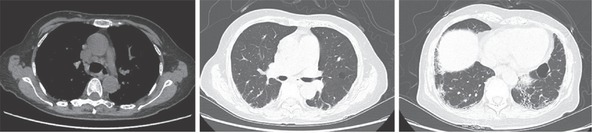

We report a case of a 68-year-old woman with chronic and severely destructive arthritis for 8 years with imaging features mimicking psoriatic arthritis (PsA) but serological evidence of systemic lupus erythematosus. Both the lupus panniculitis-like rash and the presence of interstitial lung disease were considered manifestations of systemic involvement of SLE.

我们报告了一例68岁女性患者的病例,她患有慢性严重破坏性关节炎8年,影像学特征类似银屑病关节炎(PsA),但血清学证据显示她患有系统性红斑狼疮。狼疮泛发性皮疹和间质性肺病都被认为是系统性红斑狼疮全身受累的表现。